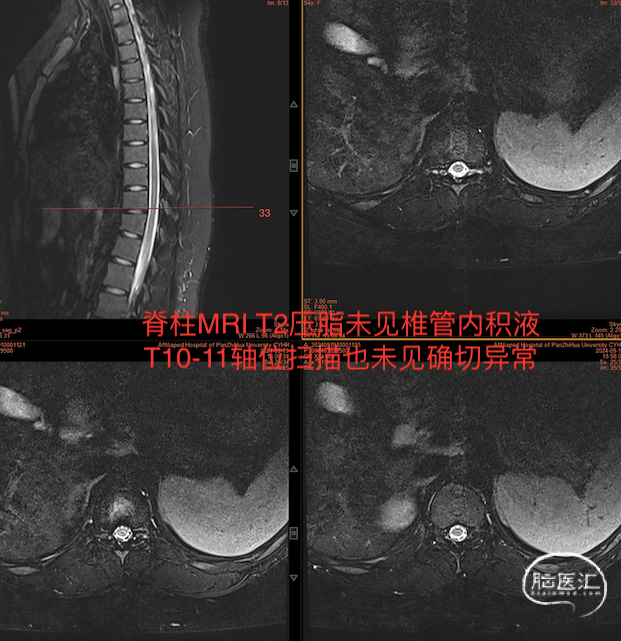

入院后头部MRI平扫及增强均未见异常,脊柱MRIT2压脂扫描如下图:

随后的水成像检查也未见异常。